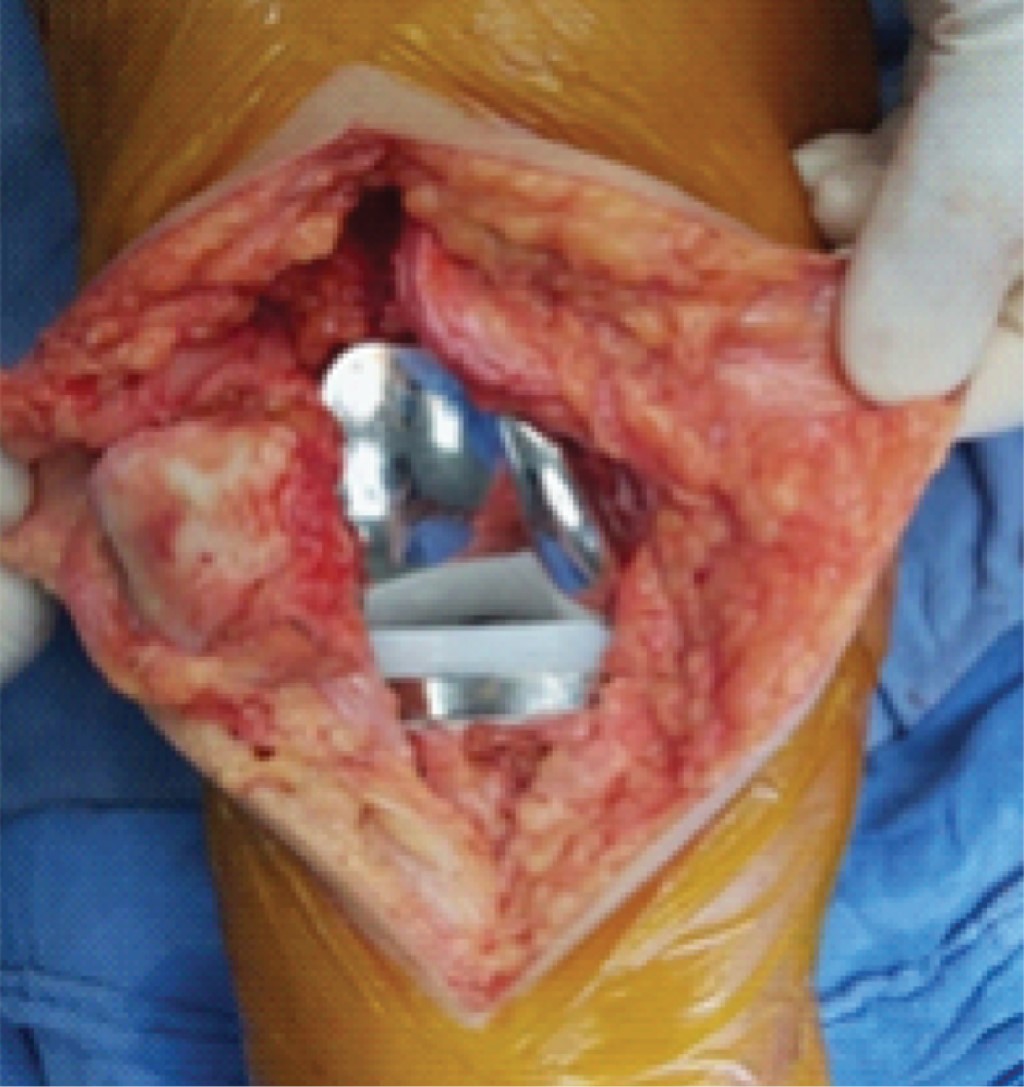

La osteoartrosis es el trastorno musculoesquelético más común encontrado en atención primaria.1 Como una enfermedad crónica está caracterizada por dolor y discapacidad física, siendo la rodilla la articulación más afectada.2 Según la OMS, afecta a 9.6% de los hombres y 18% de las mujeres > 60 años.3 En EUA, la tasa de incidencia anual estandarizada para la gonartrosis por edad y sexo por 100,000 habitantes fue de 240.4 En la mayoría de los casos, vamos a encontrar que no existe ningún factor determinante que origine la aparición de artrosis sin existir ninguna alteración articular preexistente, dentro de las causas secundarias destacan las postquirúrgicas, postinfecciosas y postraumáticas, donde desempeñan un papel fundamental las deformidades angulares residuales como el varo y valgo, que provocan distribución anormal de las cargas de peso.5 La presencia de factores de riesgo contribuye al aumento de la incidencia de la enfermedad en la población general, y se correlaciona con el grado de dolor articular experimentado por el paciente.6 Se ha encontrado relación de la obesidad y el tejido adiposo, ya que aumenta la síntesis de citocinas proinflamatorias, como el factor de necrosis tumoral alfa y las interleucinas (IL) 1, 6, 8 y 18, disminuyendo además las citocinas reguladoras como la IL-10.7 Se considera el dolor como síntoma primario y la principal causa de discapacidad funcional.8 Para la gradación radiológica de la gonartrosis se ha desarrollado la escala de Ahlbäck (Tablas 1 y 2) y la de Kellgren y Lawrence (Figura 1).9-11 La artroplastia total de rodilla (Figura 2) es considerada como el principal tratamiento y constituye al día de hoy el que consigue mejores resultados funcionales y de satisfacción a corto y mediano plazo.12 El uso de isquemia con mango neumático o elástico sigue muy arraigado en la práctica de la cirugía ortopédica, si bien es cierto que conlleva ventajas técnico-quirúrgicas, como una mejora en la visión quirúrgica al mantener un campo operatorio más limpio y reduce el tiempo operatorio, no es un procedimiento inocuo,13 ya que se le ha asociado con complicaciones trombóticas, vasculares, nerviosas, dolor intenso en el muslo, retardo en la cicatrización de la herida, cambios hemodinámicos inherentes al proceso de isquemia y reperfusión y disminución de rangos de movilidad.14,15

Figura 2